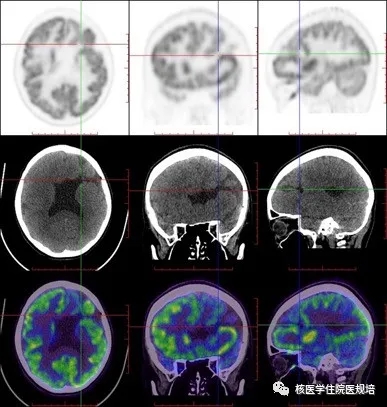

FDG PET/CT脑断层图像示:脑中线结构居中,双侧大脑皮层FDG摄取失常态,MRI所示皮层下带状灰质异位区域可见弥漫性条带状异常FDG摄取,而正常脑灰质区FDG摄取相对略减低,但皮层下核团、小脑放射性分布未见明确异常;同机CT示上述灰质异位区呈等密度改变,同时见双侧侧脑室枕角增宽,脑沟、裂及池形态未见异常。

双侧大脑皮层下弥漫性FDG代谢增高带伴脑室扩大,可符合皮质下层状灰质异位表现。